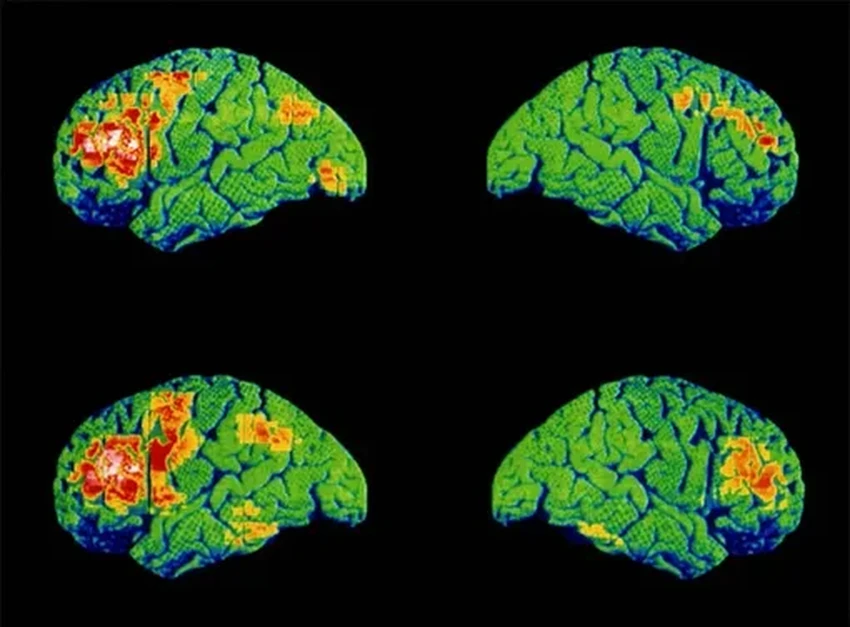

Ученые взяли под микроскоп популярный алгоритм, который часто используют для психиатрических прогнозов. Для анализа они привлекли данные пяти масштабных клинических испытаний антипсихотических препаратов. В них участвовало более полутора тысяч пациентов с диагнозом шизофрения со всего света — из Северной Америки, Азии, Европы и Африки.

Эти испытания, проходившие в 2000-х, фиксировали симптомы пациентов до начала приема лекарств и через четыре недели терапии. Исследователи обучили модель предсказывать, насколько улучшатся симптомы через месяц.